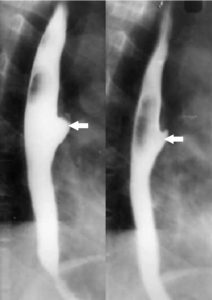

Рентген. Он позволяет оценить проходимость пищевода, состояние слизистой оболочки, ее эластичность, диаметр, а также выявить сужения или расширения. Рентгеновский метод помогает обнаружить аномалии, последствия травм и подтвердить нарушение функций пищевода.

При разрушении опухоли могут возникать сильные кровотечения, тошнота и рвота с примесью крови, а также возможно появление дырки в пищеводе, что может привести к развитию эмфиземы. Параллельно с этим могут возникать дисбактериоз, периодический стоматит и эктопия оболочки желудка. Рак пищевода может давать метастазы в лимфоузлы, легкие и печень, а также поражать костную ткань и мозг. Основные методы диагностики включают рентген и биопсию. Чем раньше онкология будет обнаружена, тем больше шансов на успешное лечение. Позднее начатая терапия может оказаться неэффективной.

Функциональное расстройство возникает при поражениях центральной нервной системы, таких как нейросифилис или инсульт, а также после отравления алкоголем или свинцом. Одним из признаков атонии является невозможность глотать твердую пищу. Для диагностики этого расстройства проводится рентгенография. Болезни пищевода часто сопровождаются гликогеновым акантозом — овальным белым образованием вдоль пищевода, которое приводит к его утолщению.